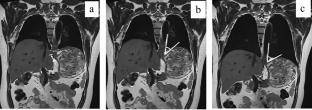

In the prospective study, 40 healthy volunteers and 30 GERD patients underwent real-time cine MRI using an undersampled low-angle gradient echo sequence (50 ms/frame) with deep-learning reconstruction, to monitor the gastroesophageal junction (GEJ) and observe the reflux of the contrast agent during the Valsalva maneuver. The width of the lower esophagus, the length of the lower esophageal sphincter (LES), the end-expiratory and post Valsalva maneuver His angle were measured.

There were no statistical differences between the two group either in lower esophageal width (14.06 ± 1.50 mm vs. 14.75 ± 1.57 mm, P > 0.05) or LES length (25.20 ± 1.46 mm vs. 24.39 ± 1.68 mm, P > 0.05). The end-expiratory His angle (84.45 ± 18.67°) and post Valsalva maneuver His angle (101.53 ± 19.22°), and the differences between them (17.08 ± 5.65°) in the GERD group were greater than those in the healthy volunteers (71.51 ± 18.01°, 86.09 ± 18.24°, 14.57 ± 3.88° respectively, P < 0.05). Reflux was induced in 8 cases of GERD group including 4 cases with hiatus hernia and not observed in healthy volunteers. The AUC for diagnosing GERD were 0.702, 0.737 and 0.634 for end-expiratory, post Valsalva maneuver His angle and their differences, when combined with real-time MRI was 0.823, with a sensitivity of 86.67% and a specificity of 67.50%.

Real-time MRI can display dynamic swallowing and reflux at the GEJ. The His angle can serve as a morphological indicator for diagnosing GERD with MRI.